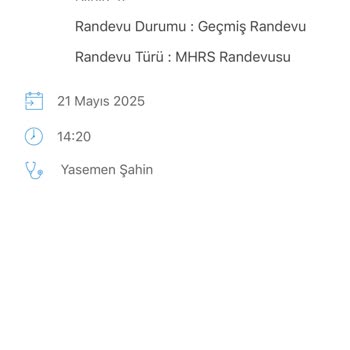

Darıca Ağız Ve Diş Sağlığı Merkezi'ne 1 Eylül 2023 tarihli randevu aldığımız özel gereksinimli 5 yaşındaki çocuğumuza uyutarak muayene ve diş çekimi yapılacağı için doktor muayene edemedi randevuyu arayarak ve detayları öğrenmek için sorduğumuz detaylı bilgi verilmedi 4 gün muayene gününü bekledikten sonra uyutarak muayene ve diş çekimi için hasta haklarına başvuru yapılıp oradan sora alınacağını söylediler dalga geçer gibi sırada 185 kişi olduğunu hepsinin durumunun acil olduğunu ve ayda 12 kişi aldıklarını söylediler yani haliyle (185:12=15.4) 15 ay sonra bize sıra gelecek herhalde çocuk iltihaptan öldükten sonra ya da bütün dişleri döküldükten sonramı bakacaklar acaba diğer özel gereksinimli çocukların ailelerine de kızıyorum böyle bir saçmalığa nasıl müsaade tahammül edebiliyorsunuz?